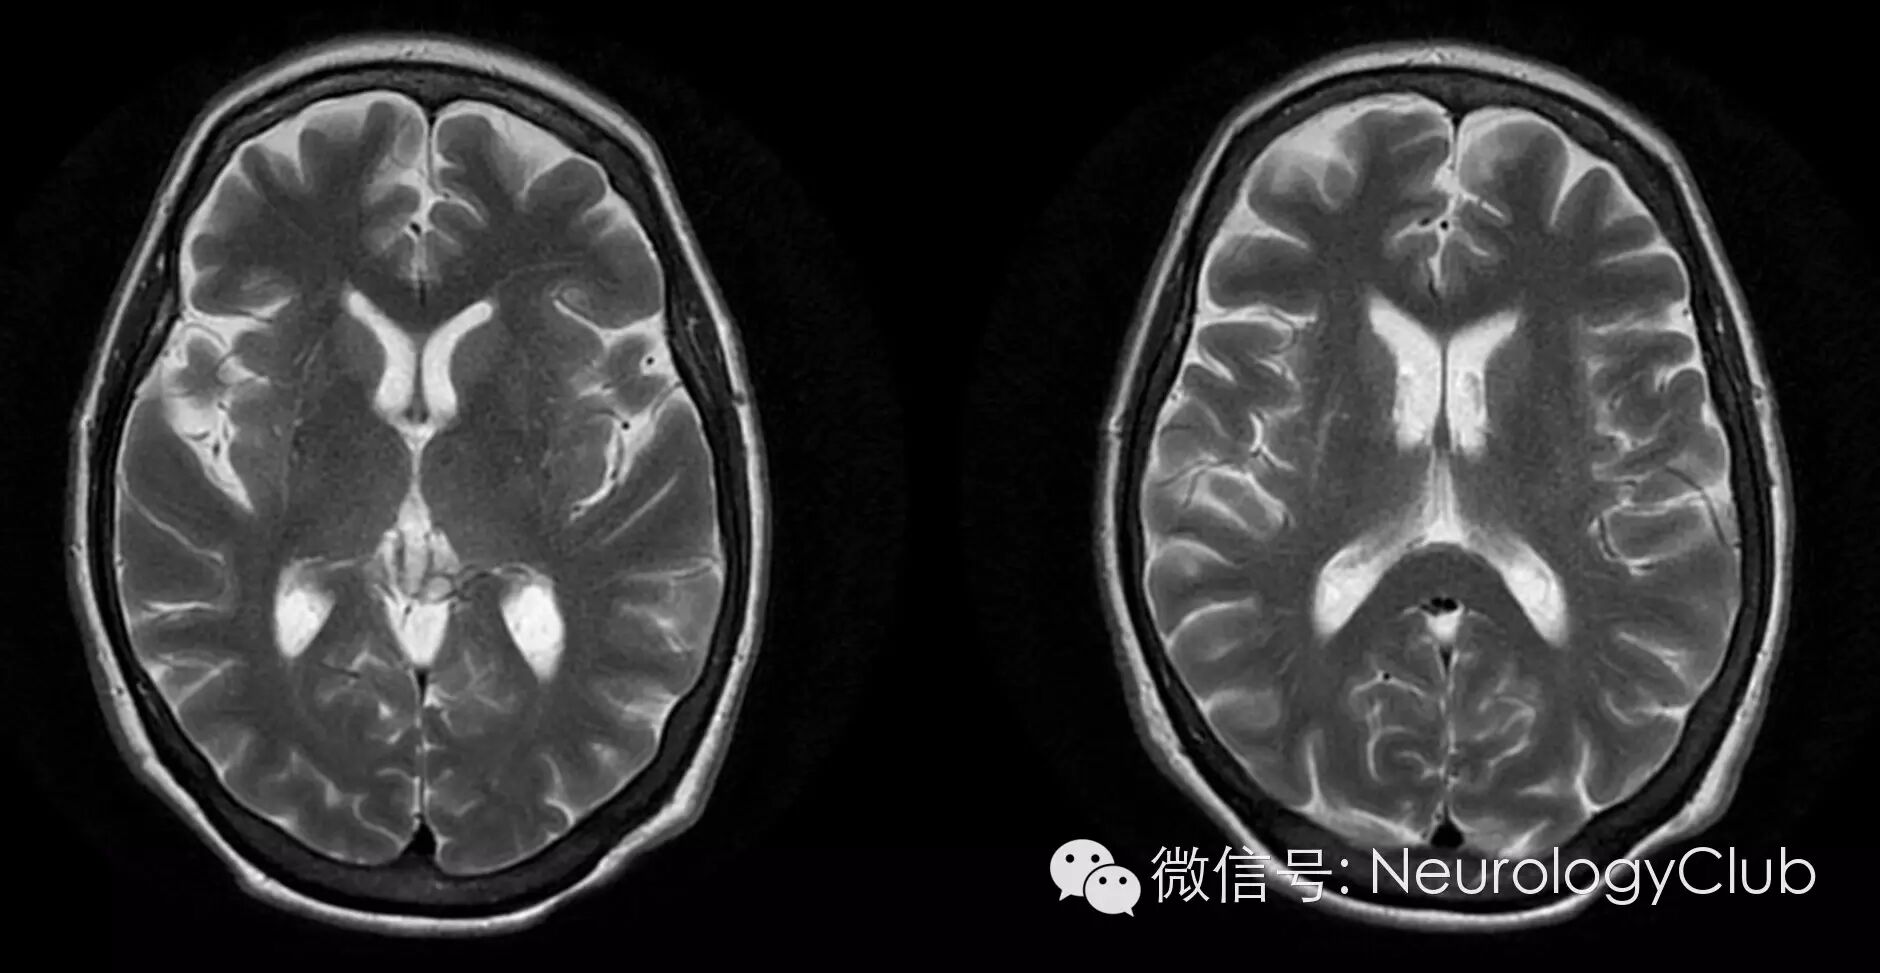

壳核T2低信号(Putaminal hypointensity

指壳核背外侧可见等于或低于苍白球信号的异常信号,病理证实是由于铁蛋白丢失、铁沉积引起。但壳核异常信号会随着磁场强度的改变而发生改变。1.5T MRI可发现壳核T1高信号,对MSA-P也有一定的诊断价值。3.0T MRI的信噪比和分辨力提高,更容易发现由铁沉积引起的T2WI低信号,因而也容易发现正常人由于退变而引起铁沉积。尽管在1.5T MRI上,壳核“间隙征”和壳核T2低信号对于诊断MSA-P有较好的敏感性和特异性,但在3.0T MRI上,这些征象的诊断价值受到一定的限制。

壳核萎缩(Putaminal atrophy

其病理基础是神经元丢失及胶质纤维增生,对于诊断MSA-P有较高的特异性。在MRI上表现为壳核变小、厚度变薄。壳核弧度消失、变直,但是壳核萎缩判断带有一定主观性,而且在病程早期敏感性不高,限制其在临床上的应用。